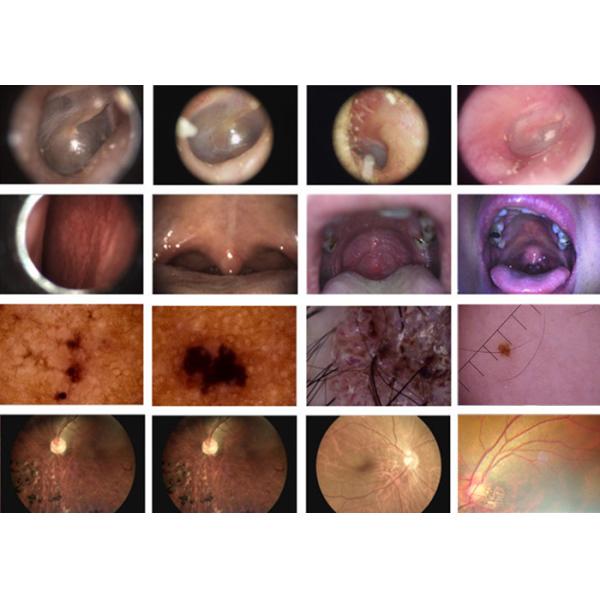

Rechargeable Portable Otoscope Ophthalmoscope Dermatoscope With SD Card Output

BS4 is one set of the full digital inspection scopes, mainly used for clinical inspection of human body.

All the images and video chips can be stored in the SD card and output to PC or laptop for saving as patients profile.

It's very convenient to compare the images and situations before and after therapy.

It is mainly used in hospital, Clinic and medical departments for doctors and nurses to examine ear, nasal and throat.

| Otoscope lens | Examine ear's canal and tympanic membrane |

| Rhinoscope lens | Examine nasal cavity |

| Laryngoscope lens | Examine throat |

Available Lens

| Digital Otoscope | Digital Dermatoscope | Digital General Imaging |

| Focus range : 5~30 mm | Focus range : 10 mm | Focus range :80 angle(diagonal) |

Rechargeable Portable Otoscope Ophthalmoscope Dermatoscope With SD Card Output Images |